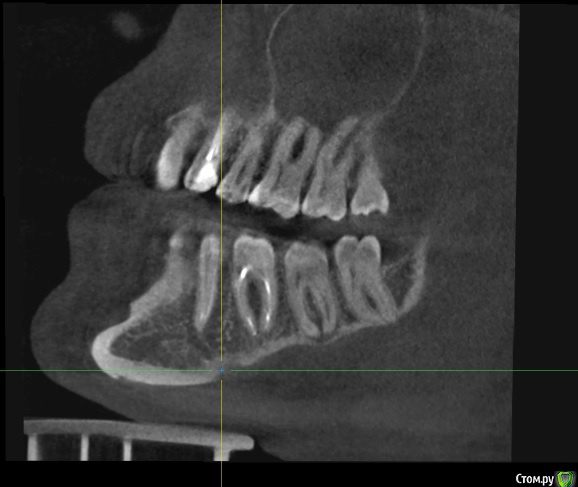

Илья Т. Опубликовано 24 июня, 2020 Поделиться Опубликовано 24 июня, 2020 (изменено) Добрый день! 3 месяца назад была проведена имплантация 21 зуба, до этого за еще за 3 месяца был удален этот зуб и в лунку заложен костный материал (т.к имплантолог изучив КТ сказал что кости не много и сверху находится пазуха, необходимо подсыпать костный материал туда). 1 июля идти с КТ на слепки, сделав вчера КТ решил посмотреть его сам и меня смутило, что в некоторых положениях справа от имплантата (где нёбо) как бы пустота? А когда подкрутив колесико на мышке как бы меняется резкость, то она пропадает? Можно ли по скринам определить нормально ли интегрировался имплантат и нормальный ли объем костной ткани? Изменено 24 июня, 2020 пользователем Илья Т. Ссылка на комментарий

Irouil Опубликовано 24 июня, 2020 Поделиться Опубликовано 24 июня, 2020 Пустота - скорее всего просто засветка от имплантата. Снимки выглядят нормально. Интеграция имплантов проверяется не по снимкам 3 Ссылка на комментарий

Илья Т. Опубликовано 2 июля, 2020 Автор Поделиться Опубликовано 2 июля, 2020 Снимки выглядят нормально.А подскажите ещё с фронтальной части достаточно объема кости? Просто где то прочитал, что чтобы имплантат долго стоял необходимо сколько то миллиметров кости вокруг него чтобы было обязательно... Ссылка на комментарий

red_butler Опубликовано 2 июля, 2020 Поделиться Опубликовано 2 июля, 2020 А подскажите ещё с фронтальной части достаточно объема кости? ДОСТАТОЧНО 1 Ссылка на комментарий

Irouil Опубликовано 17 июля, 2020 Поделиться Опубликовано 17 июля, 2020 Мёртвый зуб, требуется эндодонтическое лечение, у верхушек корней воспалительный процесс 1 Ссылка на комментарий